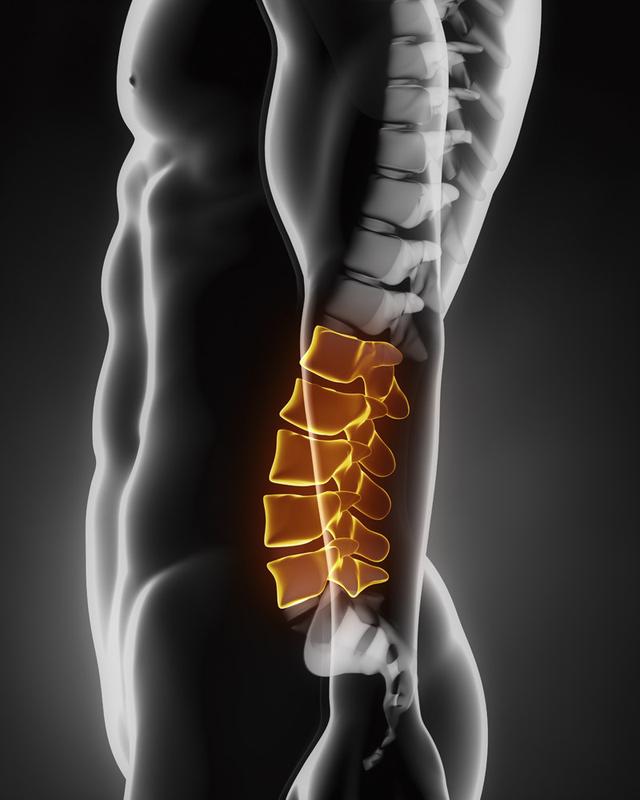

从一方面来说,人类是弱小的,容易生病,容易受伤,但从另一方面来说,人类也是强大的...